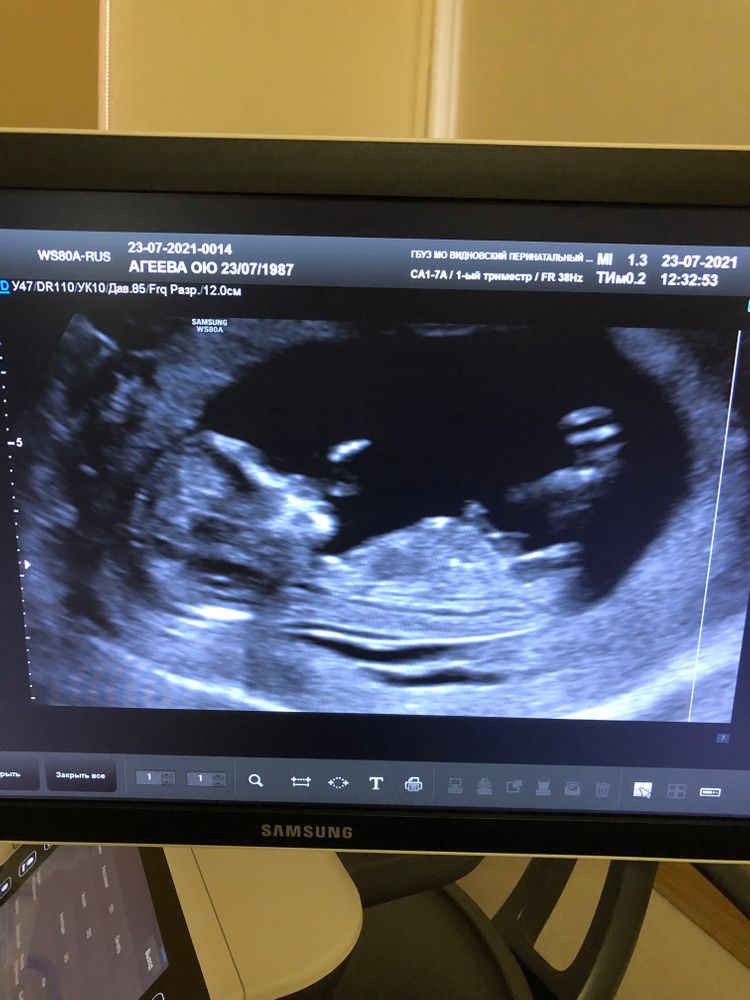

Девочки,может кто-то разбирается))возможно ли понять по узи пол малыша?)на 1 скрининге не сказали.

По бугорку девочка)

Но у нас тоже по бугорку в 11 нед девочка.

А на скрининге в 13 нед говорят мальчик.

Ждём дальше)

Девочка ,точно такой бугорок у нас и в 20 недель подтвердили что девочка

Ольга, это мы на 11+6 недели и точно как у вас ,девочка 🙈